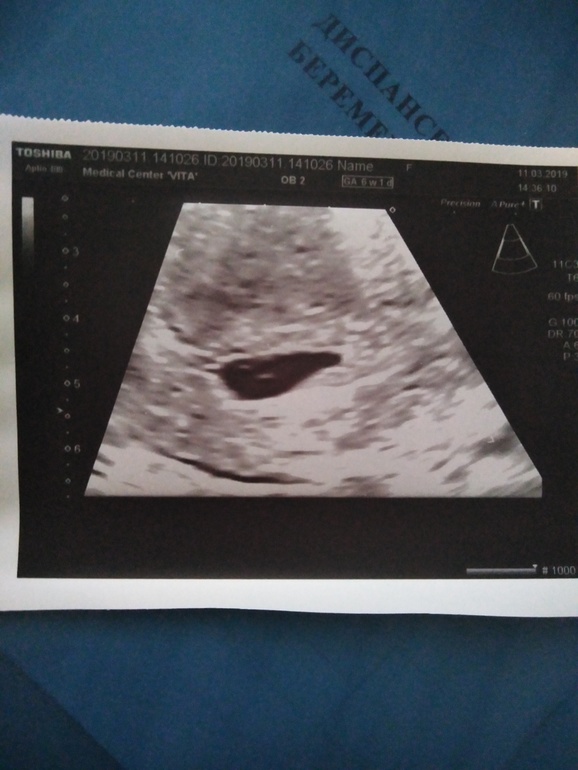

Ну токс не повод думать что опять девочка будет,,,лёгкой беременности,,, А есть фото узи первого 6,7 недель?можно погодать по методу Рамзи кто будет?

это ванинально

это сверху

Будем надеятся что МАЛЬЧИК ,,очень похоже,🙏🙏🙏🙏🙏🙏🙏🙏🙏🙏🙏✊✊✊✊✊✊✊✊✊✊отпишитесь когда будет скрининг,,буду ждать